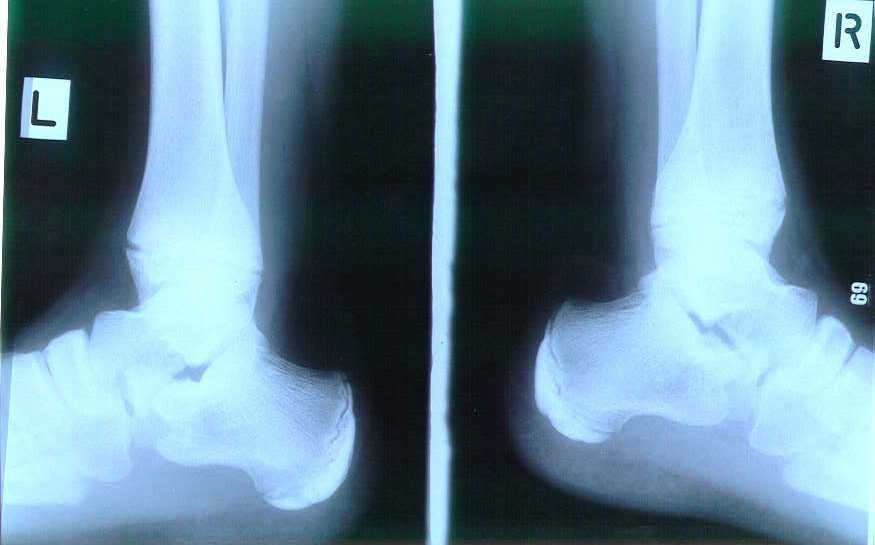

- X-ray films to rule out other conditions

- Patient x-ray films